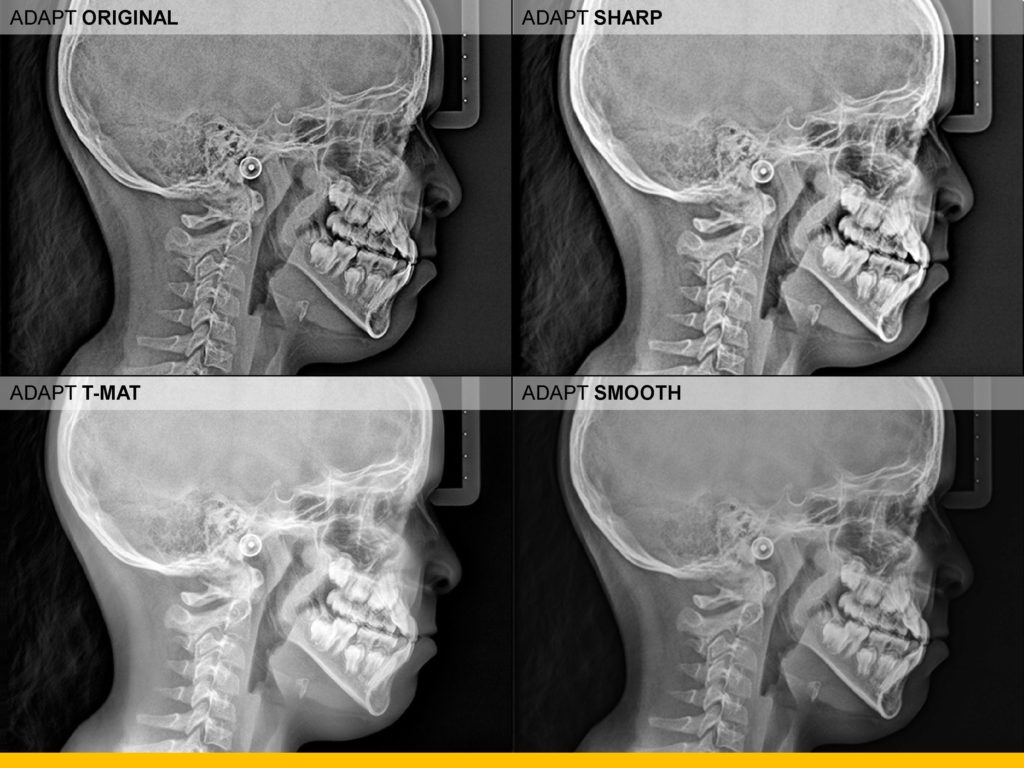

- Uz najnovije algoritme za obradu softvera, CS 8100 minimizira sjene kralježnice i proizvodi jasne, oštre digitalne slike koje su spremne za pregled gotovo odmah.

- Snažni filtri bez artefakata povećavaju kontrast i oštrinu jednim klikom